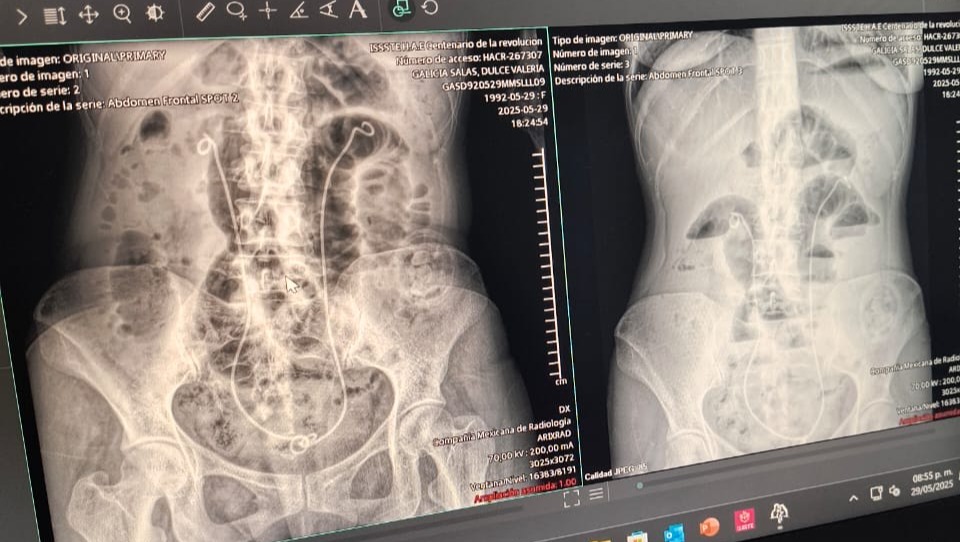

Vale fue diagnosticada con cáncer de colon etapa 3 en diciembre de 2023, y desde entonces ha enfrentado con fortaleza una colostomía, tratamientos de radio + quimioterapia, tres cirugías en el abdomen y múltiples hospitalizaciones.

In December 2023, Valeria was diagnosed with Stage 3 colon cancer. Since then, she has bravely endured a colostomy, combined radiation and chemotherapy treatments, three abdominal surgeries, and multiple hospitalizations.